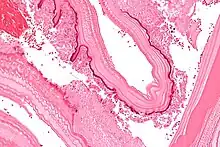

Micrograph showing the characteristic laminated cyst wall.H&E stain.